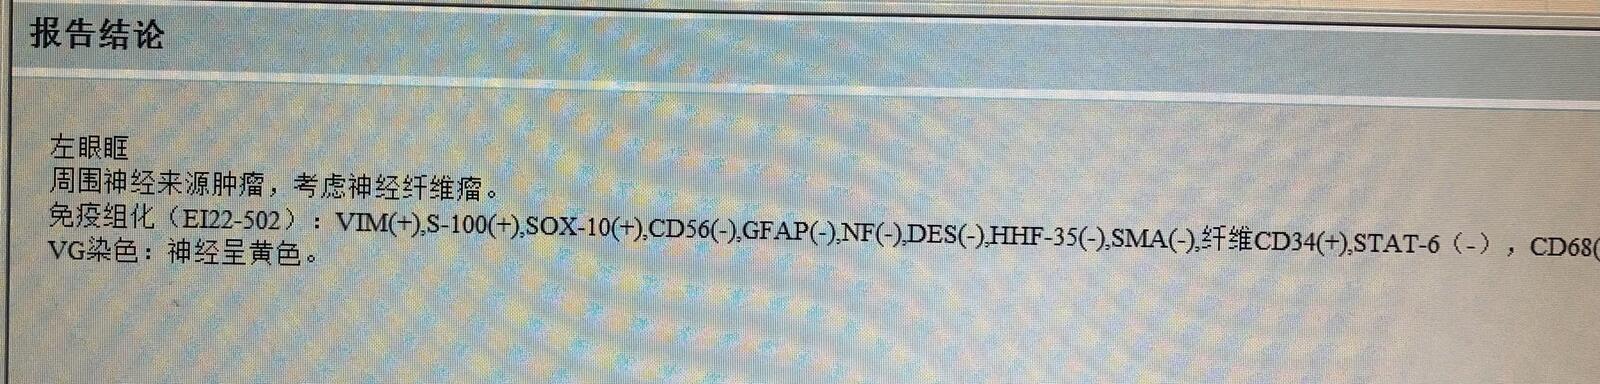

最终病理为神经纤维瘤,

其发病率远低于同为神经起源的神经鞘瘤。

需注意全身有无神经纤维瘤病的其他表现包括背部皮肤咖啡色斑及皮下结节等改变,后者一字之差即为全身性疾病。